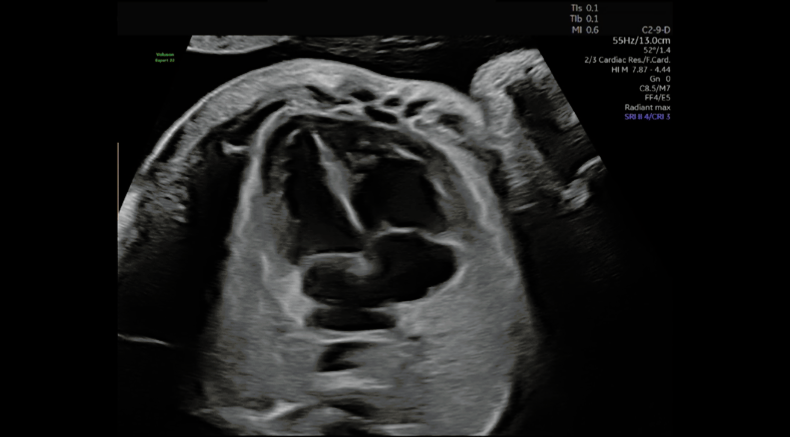

Four chamber heart view

Abu-Rustum, R. (2025, September 14-17th). The fundamental four chamber view: what you might see and what you might miss [Workshop]. 2025 ISUOG World Congress, Cancun, Mexico.